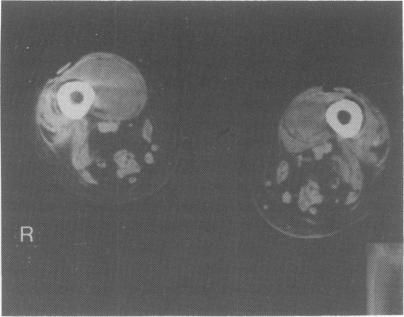

We describe a 19 year old woman with systemic lupus erythematosus on corticosteroid therapy, who developed bilateral, multiple, gas-forming Salmonella enteritidis leg abscesses and osteomyelitis mimicking deep vein thrombosis. The infection was treated successfully by a combination of surgical drainage and intravenous ceftriaxone, followed by prolonged oral pefloxacin. This rare case of gas-producing S. enteritidis emphasizes the difficulty in diagnosing such complications in active systemic lupus erythematosus.

我们描述了一名19岁接受皮质类固醇治疗的系统性红斑狼疮女性患者,她出现了双侧多发性产气肠炎沙门氏菌腿部脓肿和类似深静脉血栓形成的骨髓炎。通过手术引流和静脉注射头孢曲松联合治疗,随后长期口服培氟沙星,成功治愈了该感染。这例罕见的产气肠炎沙门氏菌病例凸显了在活动性系统性红斑狼疮中诊断此类并发症的困难。